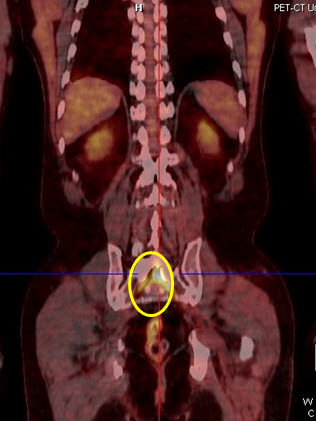

Hình 3. Bệnh nhân Lê V.T., nam, 73 tuổi. Chẩn đoán: U lympho ác tính không Hodgkin biểu hiện ở màng cứng ống tủy sống. Hình PET/CT cho thấy tổn thương tăng hấp thu FDG tại ống tuỷ sống (hình ovan).

Hình 4. Bệnh nhân Nguyễn T.V., nữ, 72 tuổi. Chẩn đoán: U lympho ác tính không Hodgkin biểu hiện tại phổi, giải phẫu bệnh là: WF6. Hình CT và PET/CT cho thấy khối u phổi trái tăng hấp thu FDG (trong vòng tròn) với max SUV=7,94.